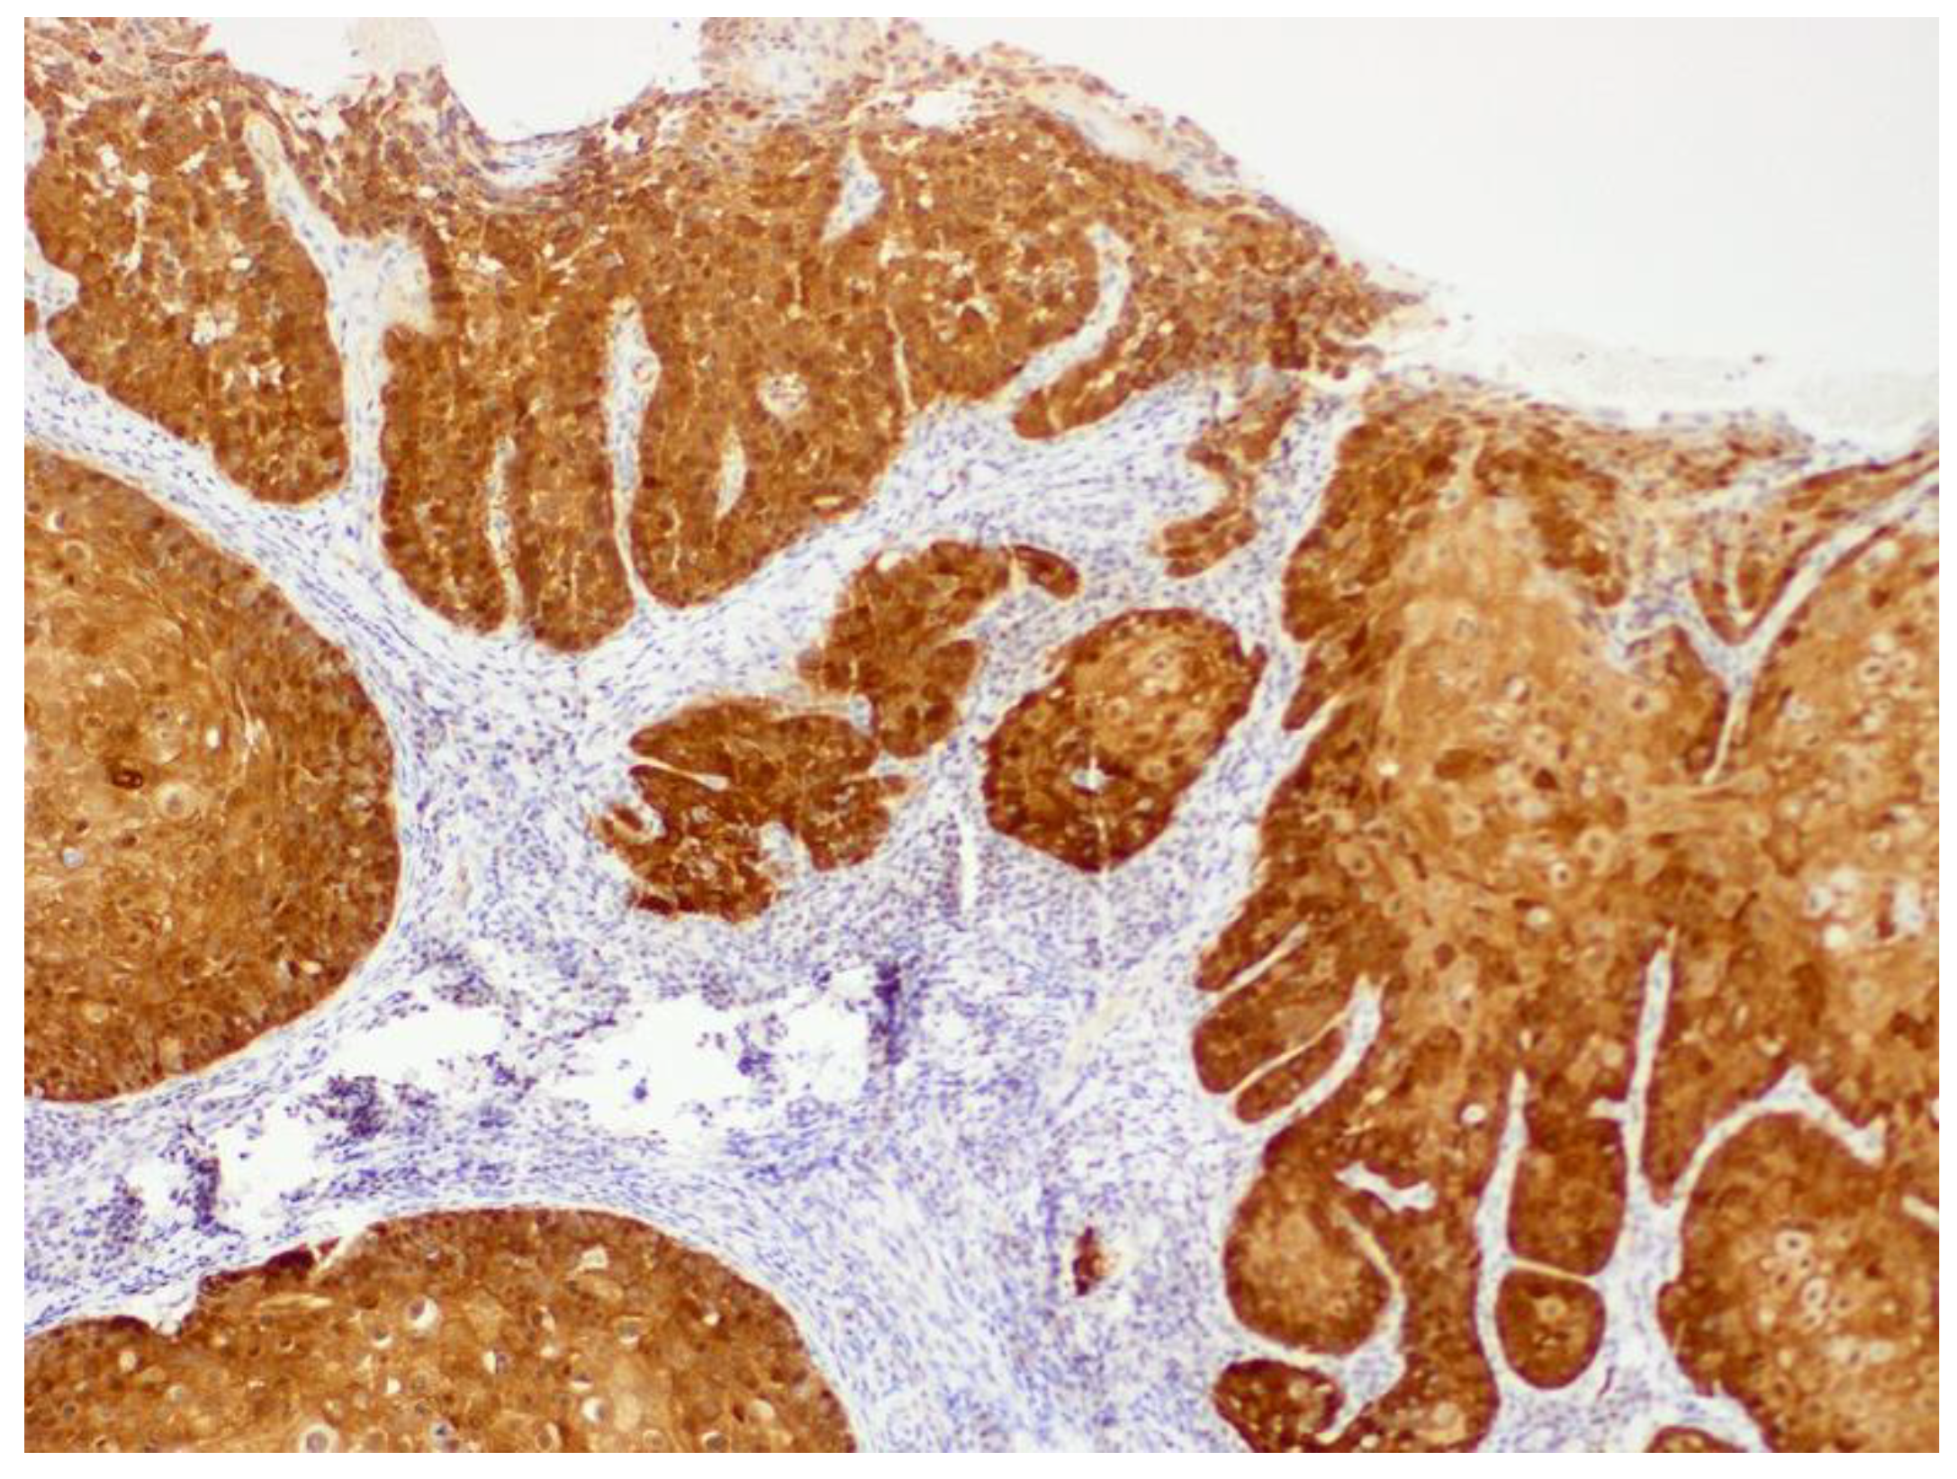

6.2. Canine Viral Cutaneous Plaques

6.3. Papillomavirus-Associated Neoplasia in Dogs

7.3. Papillomavirus-Associated Neoplasia in Cats